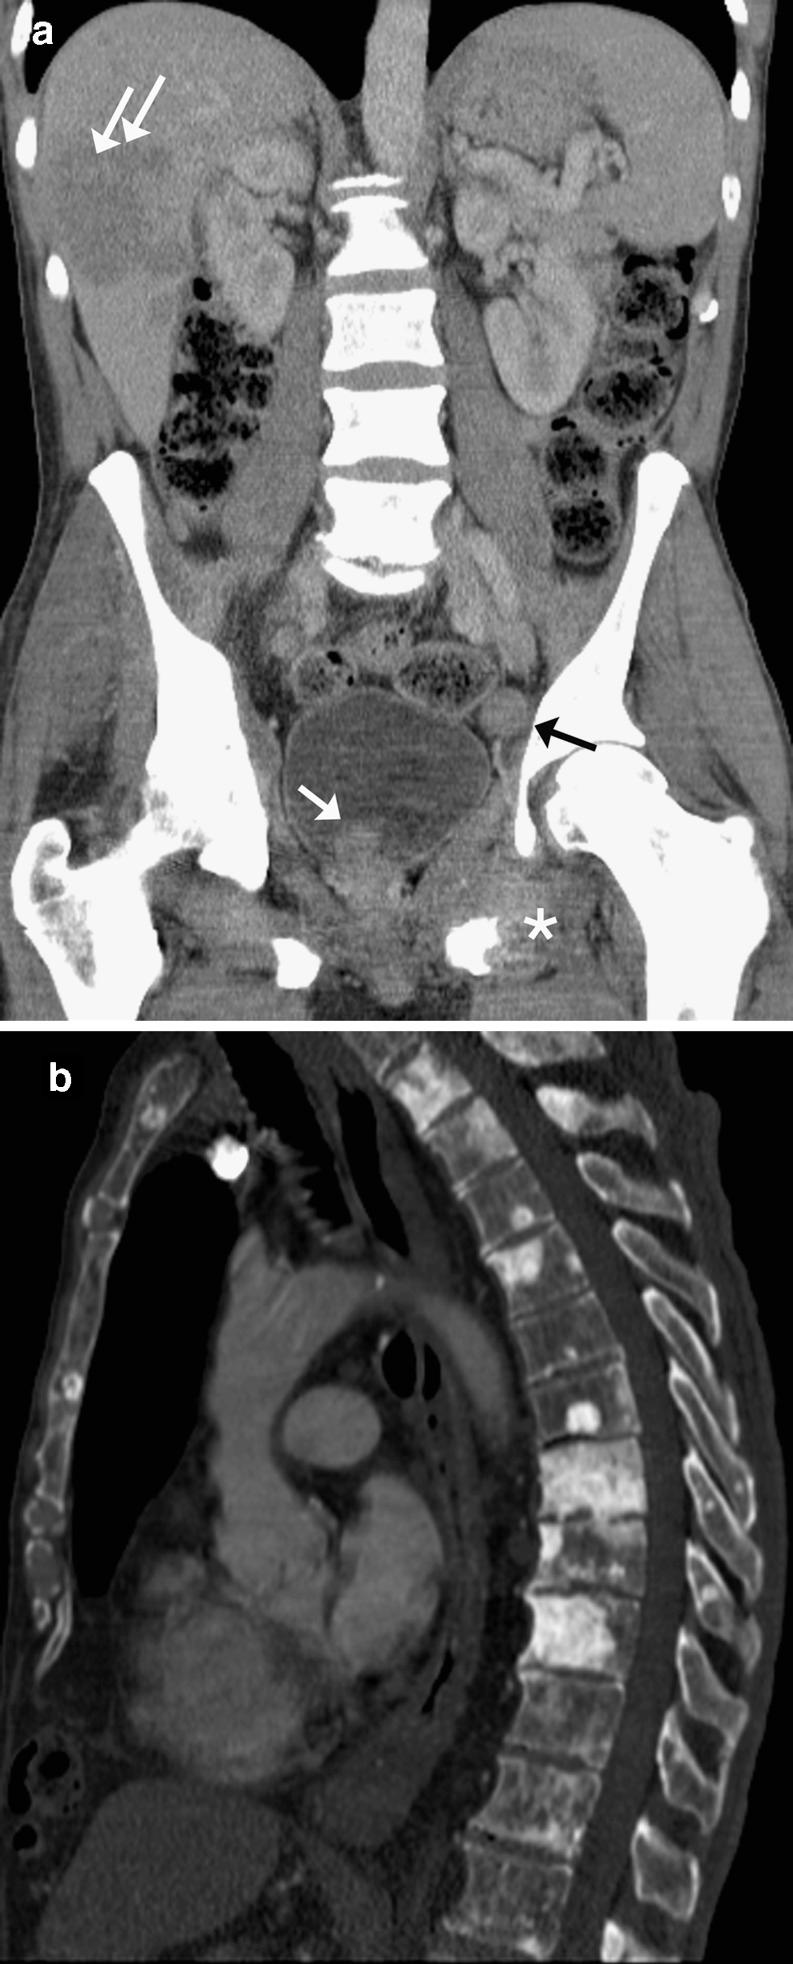

腹部和骨盆常见原发性肿瘤及其在多排螺旋计算机断层扫描上显示的肿瘤扩散模式。

Common primary tumours of the abdomen and pelvis and their patterns of tumour spread as seen on multi-detector computed tomography.

多排螺旋计算机断层扫描(MDCT)已成为许多癌症分期的主要首选检查方法。目的:本影像综述的目的是讨论腹部和盆腔内一些较常见癌症的CT影像表现,并描述其局部、淋巴结及血行肿瘤转移的典型部位。方法:将对源自胃、胰腺、结肠、肾、卵巢和前列腺的癌症进行综述。结果:了解肿瘤转移的特征部位对于准确识别所有疾病部位很重要。结论:这显然会对患者的治疗和预后产生影响。